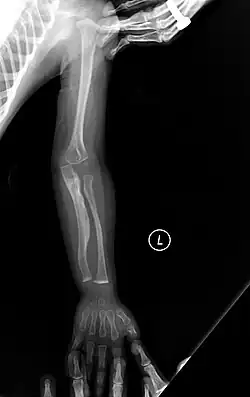

The main symptom of osteogenesis imperfecta is fragile, low mineral density bones; all types of OI have some bone involvement.[5] In moderate and especially severe OI, the long bones may be bowed, sometimes extremely so.[28] The weakness of the bones causes them to fracture easily—a study at the Endocrine Unit at the National Institute of Child Health in Karachi, Pakistan found an average of 5.8 fractures per year in untreated children.[29] Fractures typically occur much less after puberty, but begin to increase again in women after menopause and in men between the ages of 60 and 80.[1]: 486

Diagnosis is typically based on medical imaging, including plain X-rays, and symptoms. In severe OI, signs on medical imaging include abnormalities in all extremities and the spine.[97] As X-rays are often insensitive to the comparatively smaller bone density loss associated with type I OI, DEXA scans may be needed.[5]: 1514

An OI diagnosis can be confirmed through DNA or collagen protein analysis, but in many cases, the occurrence of bone fractures with little trauma and the presence of other clinical features such as blue sclerae are sufficient for a diagnosis. A skin biopsy can be performed to determine the structure and quantity of type I collagen. While DNA testing can confirm the diagnosis, it cannot absolutely exclude it because not all mutations causing OI are yet known and/or tested for.[83]: 491–492 OI type II is often diagnosed by ultrasound during pregnancy, where already multiple fractures and other characteristic features may be visible. Relative to control, OI cortical bone shows increased porosity, canal diameter, and connectivity in micro-computed tomography.[98] OI can also be detected before birth by using an in vitro genetic testing technique such as amniocentresis.[99]